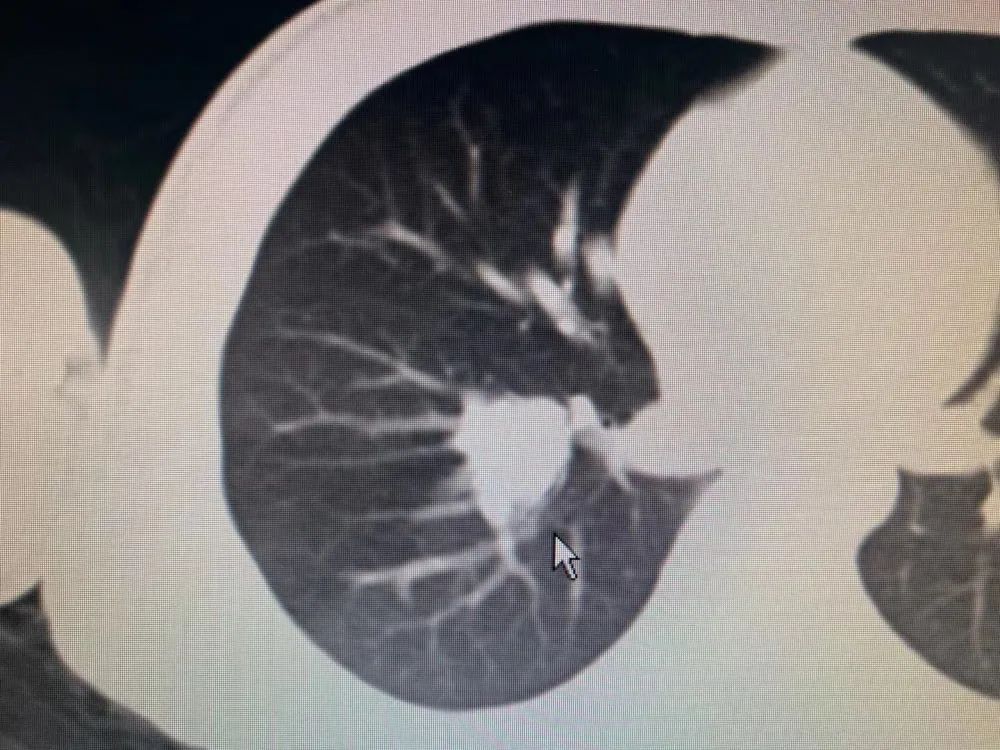

胸腹CT示:“右下肺背段结节,叶间气管旁肿大淋巴结来源可能,右下肺少许纤维条索。上腹部未见明确占位性病变”,纤支镜检查提示:“右下肺基底段支气管开口见结节状肿物,表面充血,质地脆”镜下活检示(右下叶基底段开口结节状肿物活检):结合免疫组化,考虑为涎腺源性肿瘤。

5月24日韫狄在父亲的陪同下来了广州复大肿瘤医院,隔天韫狄做了胸部、上腹部CT平扫+增强:1、考虑右肺下叶肿瘤性病变,结节大小有2.0*1.9*2.0cm,结合临床及病理检查。2、纵隔及右肺门多发稍大及小淋巴结。诊断为右肺门占位性病变。